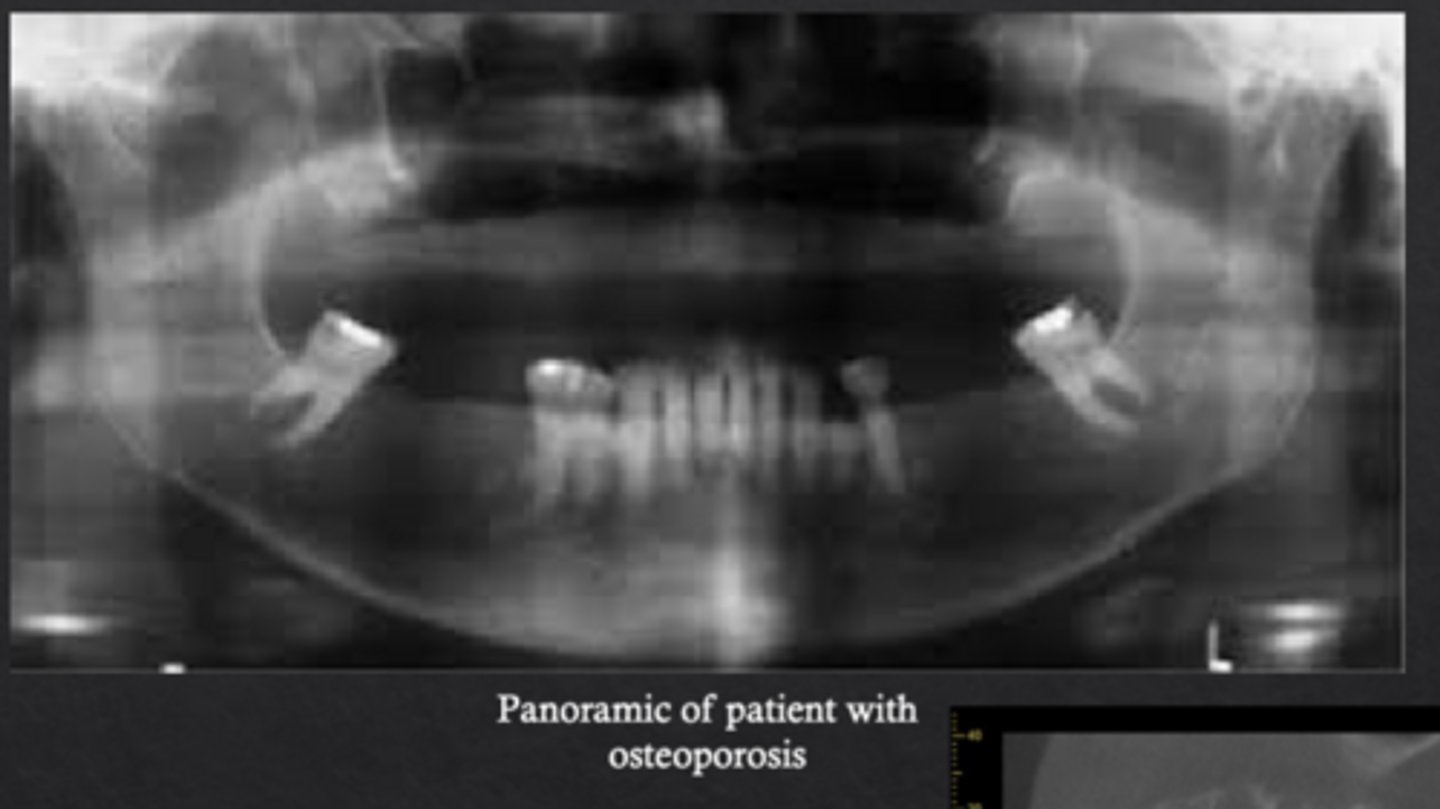

What is osteoporosis?

Systemic skeletal disease characterized by low bone mineral density and deterioration of bone microarchitecture

What radiographic changes are associated with osteoporosis?

Loss of trabecular architecture and thinning of mandibular cortical bone